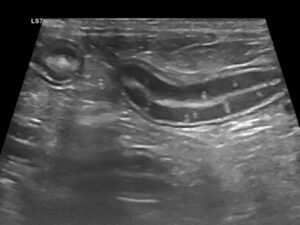

La ecografía abdominal es de gran ayuda, ya que la presencia de engrosamiento de la mucosa intestinal es frecuente en EII y linfoma intestinal difuso, mientras que la aparición de estriaciones hiperecogénicas en la mucosa se relaciona con la presencia de linfangiectasia en más del 90 % de los casos10 (imagen 2).

Imagen 2. A y B) Ecografías de un bulldog francés de 8 años con signos clínicos compatibles con EPP, en las que se aprecian estriaciones hiperecogénicas en la mucosa, que en la mayoría de los casos se corresponden con linfangiectasias, que posteriormente se confirmaron mediante histopatología. C) Ecografía de una perra mestiza con hipoalbuminemia grave asociada a una enteropatía inflamatoria. Puede apreciarse una hiperecogenicidad marcada y difusa de la mucosa intestinal, así como la presencia de efusión abdominal.